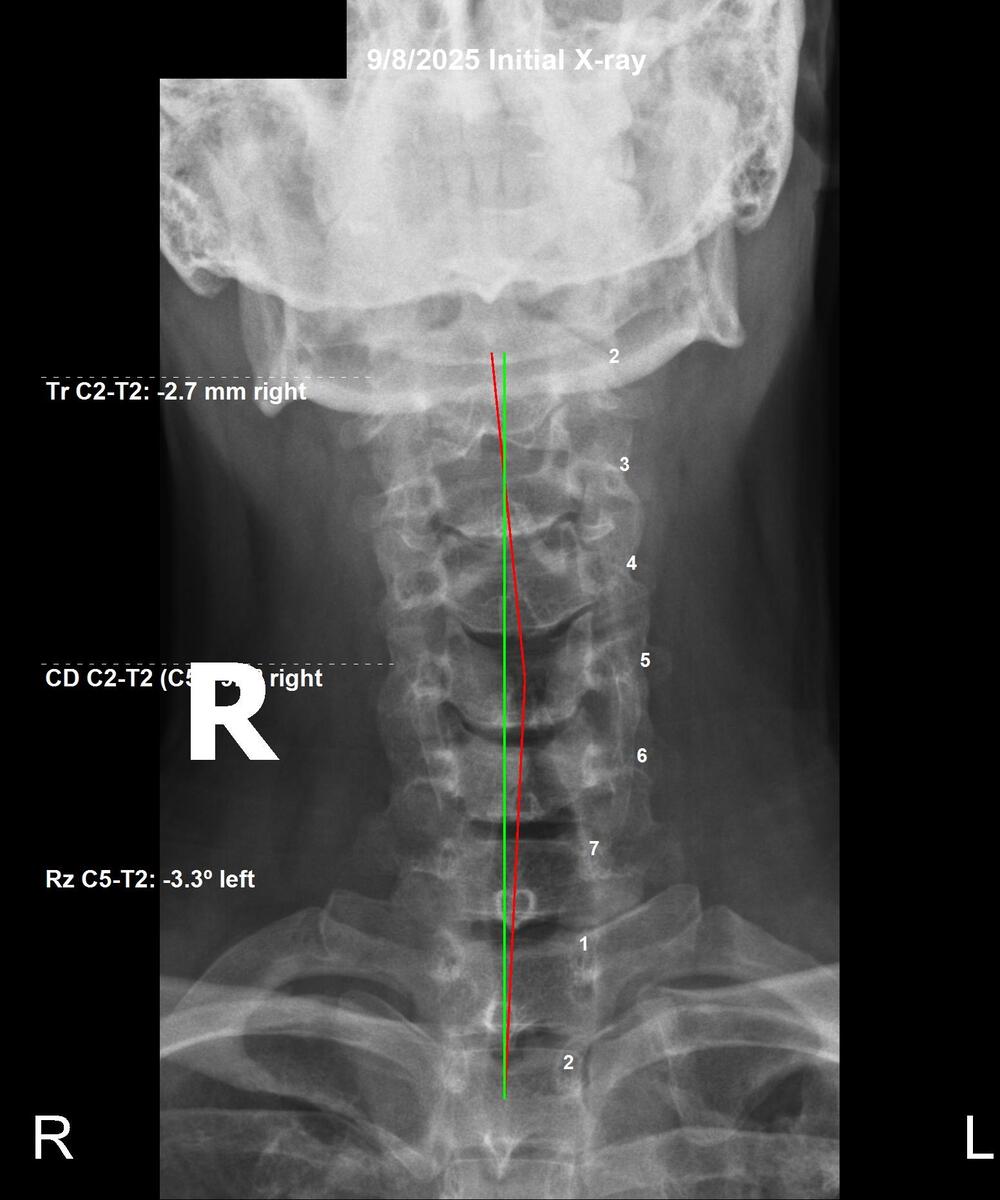

Initial cervical AP X-ray showing 2.7mm right head tilt and subluxation at C2, September 8 2025, Rochet Family Chiropractic Royal Palm Beach

Before — Sept 8, 2025

Cervical: Severe right head tilt (2.7mm deviation at C2-T2). Subluxation with rotational component, crushing nerve roots.